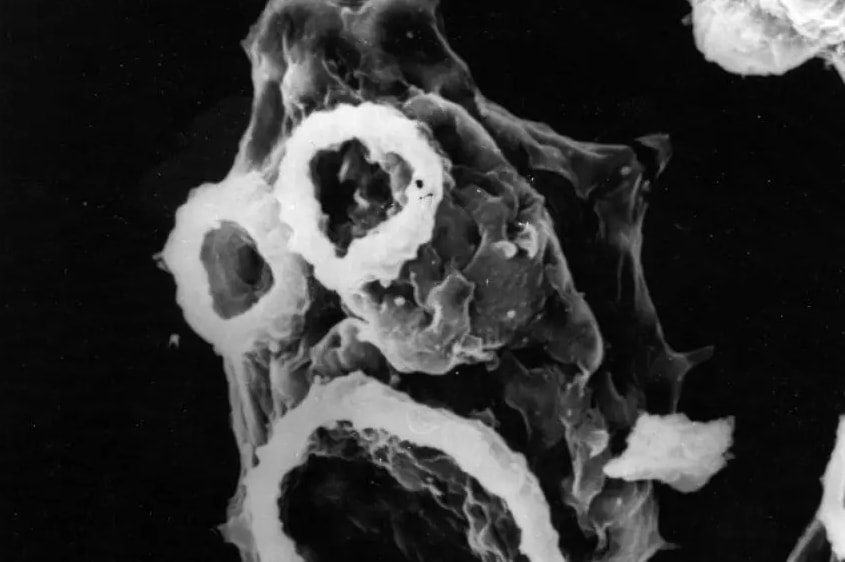

Амеба — это одноклеточный организм, который постоянно ищет бактерии и другие питательные вещества. Некоторые амебы являются паразитами, другие живут в воде или почве. Большинство из них безвредны для человека, но есть и такие, которые могут вызвать серьезные заболевания.

Заражение происходит через нос. Чаще всего это происходит во время купания, особенно когда люди ныряют вперед ногами и не закрывают нос. Амеба проникает в организм через обонятельный нерв и кровеносные сосуды, достигая головного мозга. Там она начинает размножаться, вызывая воспаление и разрушение тканей.